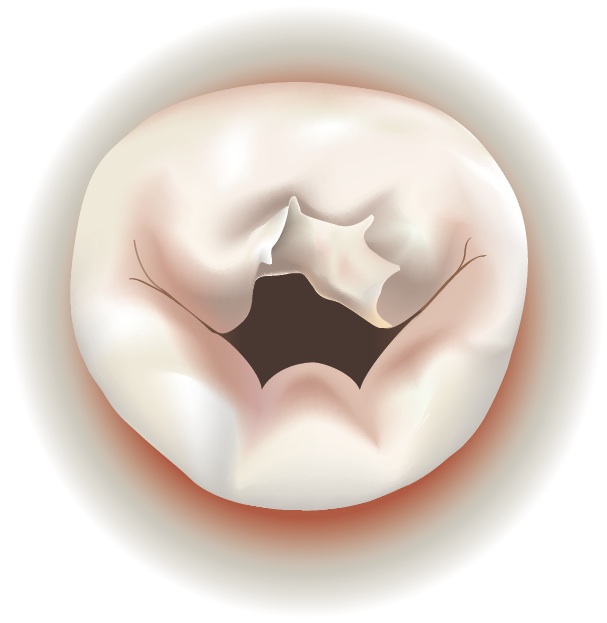

Degenerative mitral valve disease is a common disorder affecting around 2% of the population. Common findings include a “prolapse” ( slipping or falling our of place), due to elongation or rupture of the chordal apparatus. When the two leaflets fail to close tightly, the mitral valve becomes insufficient, sometimes allowing blood to leak back into the atrium from the ventricle.

A prolapse can occur on either the anterior (front) leaflet or the posterior (rear) leaflet. Usually, the annulus, where the leaflets attach, is also dilated or enlarged.

| Mitral Valve Prolapse on Anterior Leaflet | Mitral Valve Prolapse on Posterior Leaflet |